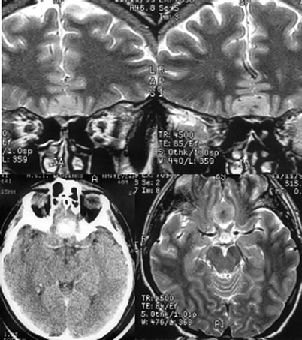

Менингиомы медиальных отделов крыльев основной кости (переднего наклоненного отростка) часто обрастают внутреннюю сонную артерию (рис. 8), внедряются в канал зрительного нерва, распространяются на диафрагму турецкого седла. Удаление их представляет сложную задачу, в отдельных случаях радикальное удаление таких опухолей неосуществимо. Применение системы интраоперационной нейронавигации позволяет локализовать включенную в опухоль внутреннююю сонную артерию и снижает риск ее ранения.

Рисунок 8. Менингиома медиальных отделов крыльев основной кости (вверху — МРТ, Т2-взвешенные изображения; внизу — правосторонняя селективная каротидная АГ, артериальная фаза. Стрелкой показано сужение просвета внутренней сонной артерии)

Гиперостотические инфильтративные менингиомы крыльев основной кости представлены, как правило, гиперостозом крыла основной кости различной степени выраженности и мягкотканными компонентами по обе стороны от гиперостоза (рис. 9).

Рисунок 9. Гиперостотическая менингиома крыльев основной кости справа с формированием мягкотканного компонента в глазнице, средней черепной и подвисочной ямках. КТ (вверху) и МРТ (внизу), с контрастным усилением)